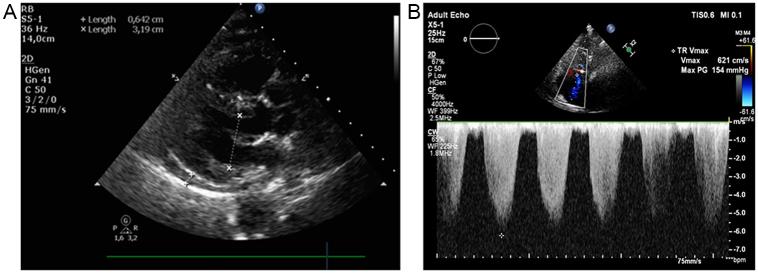

Our patient underwent high-risk surgery because, first, a large abdominal procedure was performed, and second, the operation was performed without the possibility of special preoperative modification therapy. The third, PH severity was very advanced, with higher pulmonary artery pressure than systemic blood pressure. Patients with advanced PH could experience a relatively smooth intra-operative course in non-cardiac surgery when managed with current operative and anesthetic strategies, as in the case described.

我们的患者接受了高风险手术,原因如下:首先,进行了大型腹部手术;其次,手术在没有特殊术前改良治疗可能性的情况下进行。第三,PH严重程度非常高,肺动脉压高于体循环血压。如本病例所述,采用当前的手术和麻醉策略管理时,晚期PH患者在非心脏手术中可能经历相对平稳的术中过程。